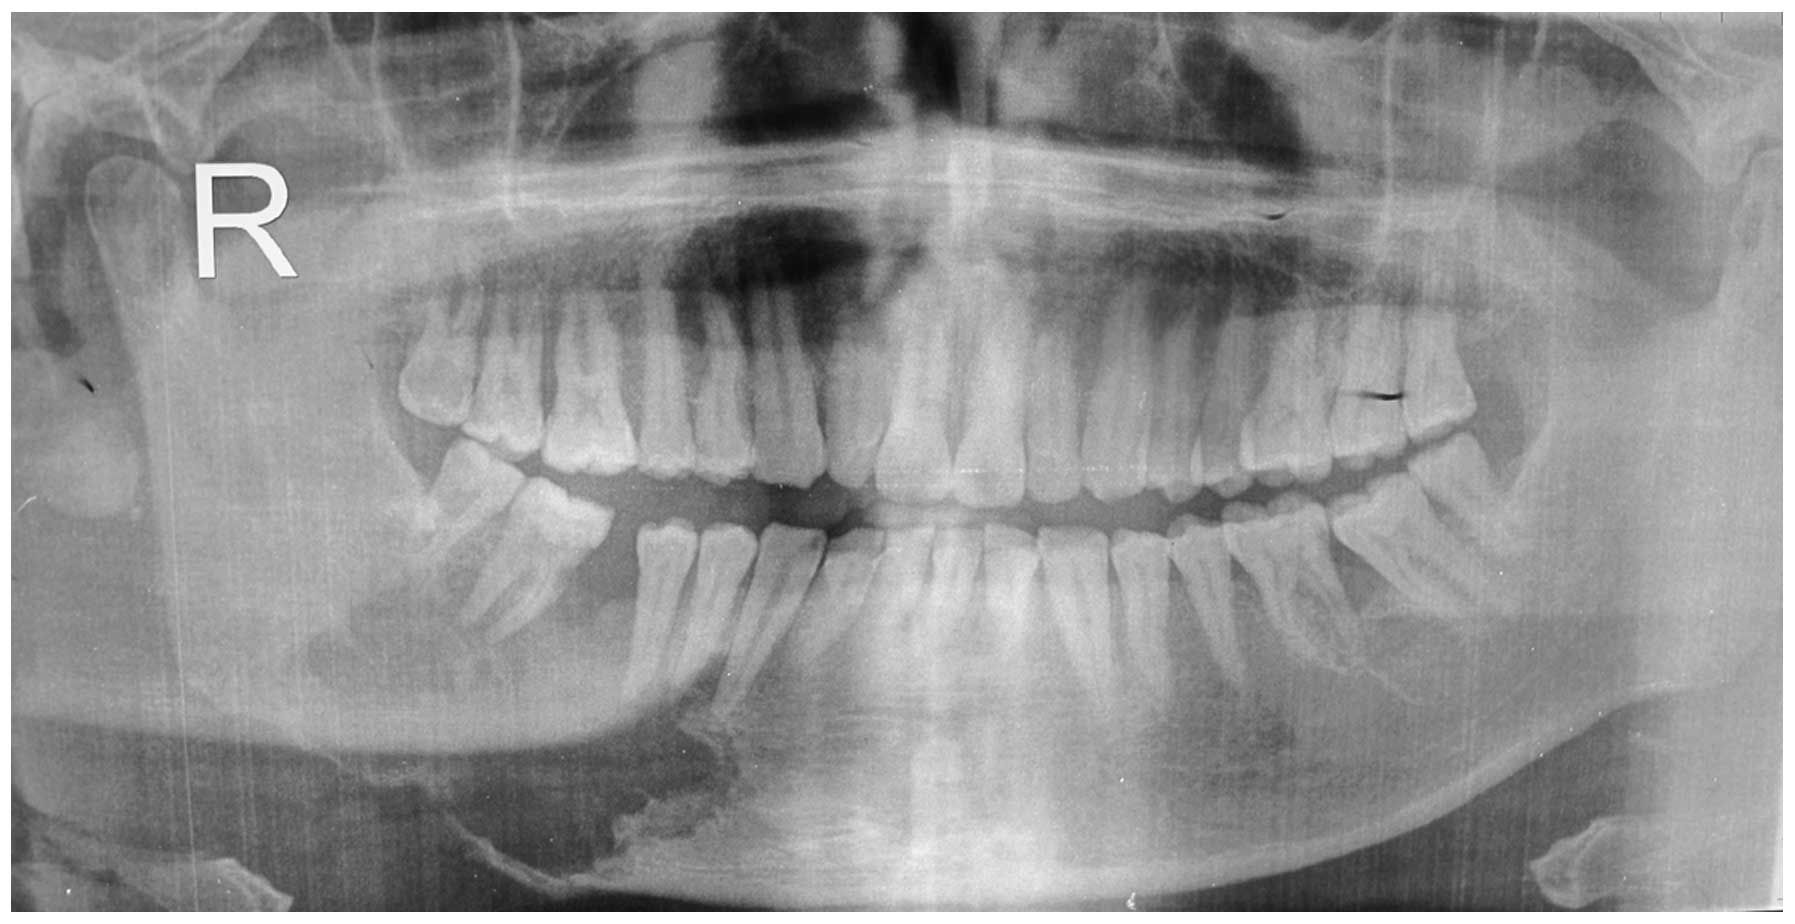

Рентгеновские снимки посттравматического остеомиелита челюсти: Медицинские случаи

Раздел: Образы вокруг